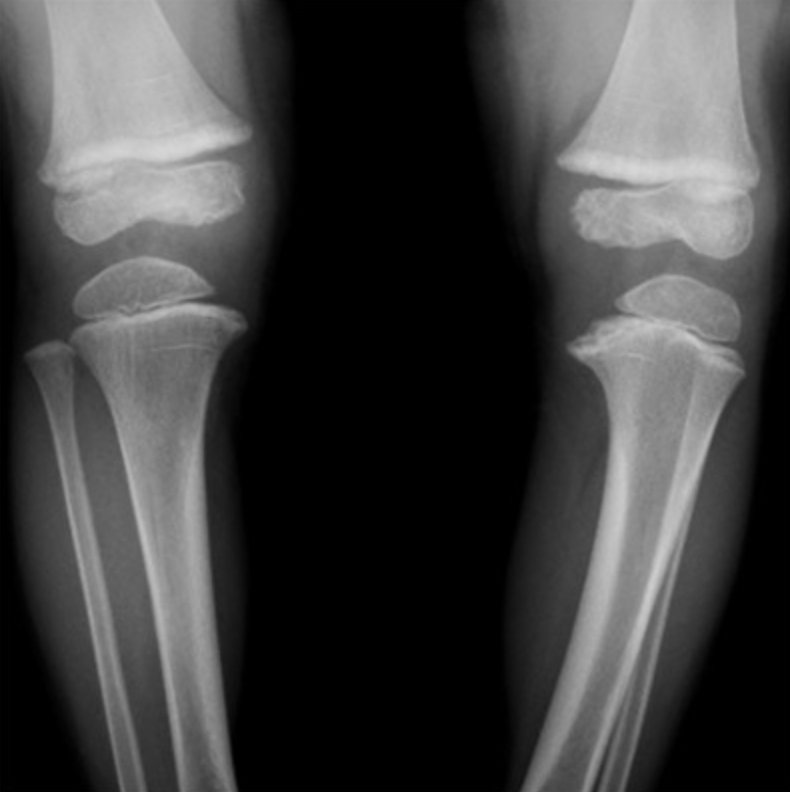

Blount Disease

• Abnormal ossification of posteromedial portion of proximal tibial physis

• Beaking, widening, irregularity of medial aspect of proximal tibial physis

• Tibial varus deformity

• Commonly bilateral